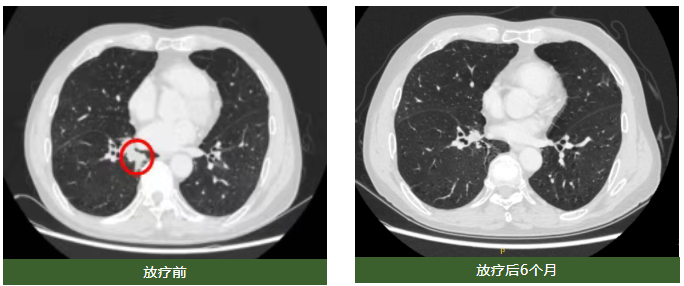

由于长期肺结核病史,马大爷的肺功能严重受损,临床评估不适合手术,也无法耐受化疗。立体定向放疗团队经过充分讨论,认为对于这类因肺功能欠佳而不适合手术的早期肺癌患者,射波刀立体定向放射治疗可利用呼吸追踪技术,可对早期肺癌进行精准聚焦照射,达到手术治疗疗效。经射波刀立体定向放疗(Dt=8Gy/次,共5次)后,6个月复查CT,马大爷右肺下叶的病灶消失,且未出现放射性肺炎等不良反应,存活至今已满4年。